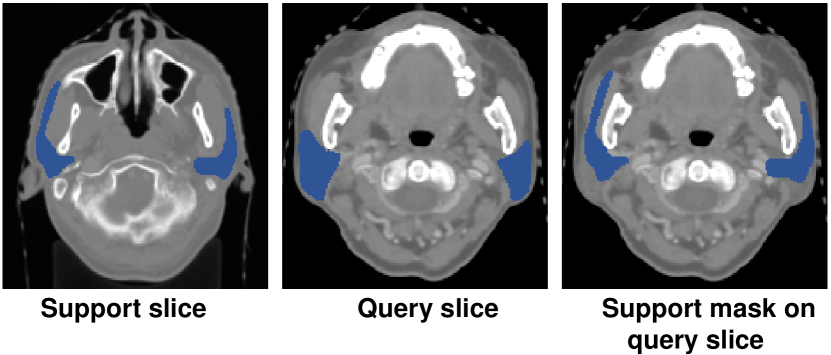

Figure 4: Visualization example of low intersection of parotid glands between support and query slices in StructSeg19.

Without being indicated the range of slices where the organ lies, our proposed PRNet outperforms others largely, especially in StructSeg19. There are mainly 2 reasons: (1) SE-Net passes the support set through the conditioner arm, whose information is conveyed to the segmenter arm via interaction blocks. It assumes that the target organ in the support slice is roughly aligned with the one in the query. However, due to the limited volume size of organs in HaN, even slight intersecting pixels of target organs between support and query slices caused by small variance among patients could make the above assumption unsatisfied. Fig. 4 presents an visualization example of parotid glands. It could be observed that the propagation of the support mask on query slice has a small overlap with the ground truth; (2) SSL-ALPNet utilizes a self-supervised superpixel segmentation task then uses the learned representations to segment new classes without fine-tuning. However, as shown in Fig. 5, the contrast of organs, e.g., brain stem in StructSeg19 with surrounding tissue, is extremely low even after normalization, which is vital to SSL-ALPNet because it could hardly select superpixels distinguishing the boundary of target organs during training time. In contrast, our method first locates fore-/background scribbles in query volumes, thus is not sensitive to the extreme sample imbalance and low contrast.